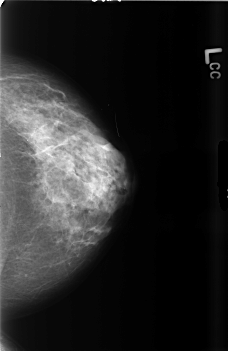

B_3464_1.LEFT_CC

LEFT_CC LINES 4552 PIXELS_PER_LINE 2952 BITS_PER_PIXEL 12 RESOLUTION 50 NON_OVERLAY